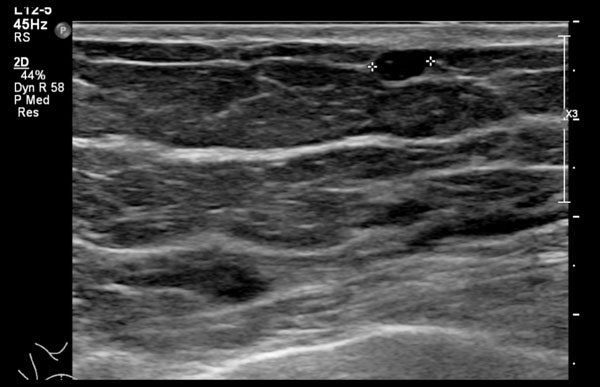

Hình ảnh cho thấy một tổn thương trống âm, có thể hơi giảm âm với thành hơi không đều và dày.

Tuy nhiên, vẫn có tăng âm phía sau, khiến chúng tôi nghĩ rằng đây có thể là một nang.

Chọc hút đã được thực hiện và nang được hút hoàn toàn, đây là bằng chứng cuối cùng xác nhận chẩn đoán.